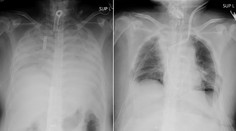

Pľúca Porovnanie snímok pľúc je šokujúce: Po-covidové sú oveľa horšie ako pľúca tuhých fajčiarov Jana Habarová 17. 1. 2021